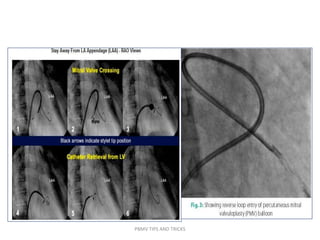

• When the puncture site is moved to the left,

downwards or too close to the MV, the alternatives to

cross the balloon are reverse loop method.

• Another approach in this situation is first crossing the

MV and placing the 0.20 backup J-tipped wire in LV and

then introduction of diagnostic JR coronary catheter

over this wire.

• Then positioning of the preshaped 0.25 coil wire in LV

and then introduction of Inoue balloon over the wire